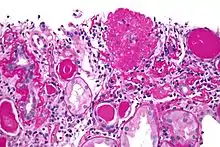

Light micrograph of focal segmental glomerulosclerosis, hilar variant. Kidney biopsy. PAS stain.

On histology, FSGS manifests as scarring (sclerosis) to segments of glomeruli; moreover, only a portion of glomeruli are affected.[7][20][21] The focal and segmental nature of disease seen on histology help to distinguish FSGS from other types of glomerular sclerosis.[21]

Diagnosis of FSGS is made by renal biopsy that includes at least fifteen serial cuts with at least eight glomeruli.[31][32] Histologic features include sclerosis (scarring) of a portion (average: 15%) of the glomerular space, with only a portion of glomeruli manifesting any sclerosis.[32]